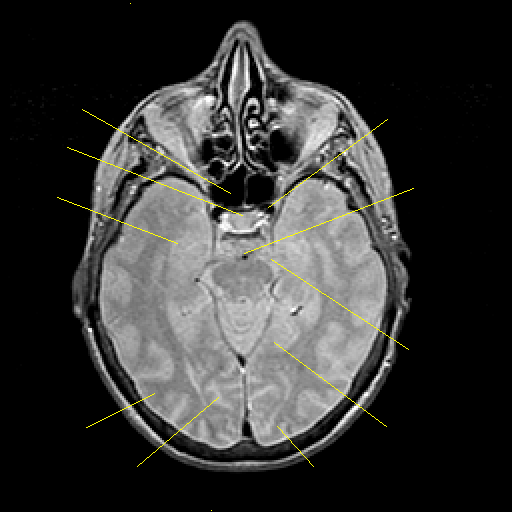

Proton density-weighted structural MR: Slice 20

Slice 20

Pointers

Labeled